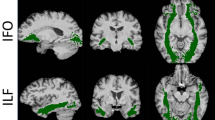

White matter profiles

Significant, symmetrical white matter alterations were identified in PLS group, primarily involving the corticospinal tracts and the corpus callosum. Cerebellar, fornix, brainstem and temporal lobe alterations were also captured. Fig. 2. ROI analyses also demonstrated widespread diffusion abnormalities in the PLS group (Table 3). Across all diffusion metrics, the most significant changes were observed in the corticospinal tracts and in the body of the corpus callosum. Thalamic white matter involvement was also detected across all diffusivity measures. While no white matter region-of-interest was entirely preserved, parietal and occipital lobe involvement was relatively spared.

Our voxelwise and ROI white matter analyses not only confirm the pathognomonic degeneration of the pyramidal tracts, but capture extra-motor white matter changes across multiple diffusivity metrics. Tract-based spatial statistics readily capture the degeneration of the body of the corpus callosum, but the ROI analyses also demonstrate the forceps minor (anterior forceps) and forceps major (posterior forceps) are also significantly affected. The tract-based analysis of AD, MD and RD captured considerable fornix pathology which has not been previously reported in PLS. The fornix is a key output tract of the hippocampus and its degeneration has been linked to memory deficits in ALS (Christidi et al. 2019). The observation that both the hippocampus and its output bundle are affected illustrates the concomitant degeneration of interconnected brain regions (Bak and Chandran 2012). Tract-based spatial statistics also identified diffusivity changes within the thalamus, which is typically by either evaluated by volumetric (Finegan et al. 2020c) or vertex-wise (Finegan et al. 2019d) approaches relying on T1-wieghted raw data. In this study we found both thalamic diffusivity alterations – reduced FA, increased AD, MD, RD - as well as volume reductions on structural analyses. Both imaging and post mortem studies suggest that thalamic changes are driven by the focal degeneration of specific nuclei as opposed to global atrophy (Chipika et al. 2020b; Chipika et al. 2020c). One the benefits of combining whole-brain and ROI analyses is the ability to rank the most affected and least affected brain regions. Similarly to ALS (Bede et al. 2016), PLS also exhibits a strikingly selective pattern of frontotemporal vulnerability with the relative sparing of postcentral and lateral occipital brain regions. Despite the considerable symptom duration profile of this cohort, parietal and occipital white matter involvement is limited in this patient group. The white matter changes identified in the brainstem (Fig. 2.) are not surprising in light of the UMN burden and pseudobulbar manifestations observed in the cohort and are consistent with dedicated brainstem studies (Bede et al. 2020; Bede et al. 2019). Cerebellar grey matter atrophy has been previously described (Finegan et al. 2019a) based on imaging data, but it is seldom assessed specifically clinically. The clinical relevance of cerebellar pathology may be underestimated in PLS where a significant proportion of patients use walking aids for safe ambulation and may be at a relatively high risk of falls. Cerebellar pathology was also detected on tract-based and ROI white matter analyses. While the clinical detection of subtle cerebellar signs may be confounded by prominent pyramidal signs the target evaluation of cerebellar function may be judicious. Cerebellar degeneration has also been implicated in the aetiology of pseudobulbar affect through impaired gate-control mechanisms (Bede and Finegan 2018; Christidi, Karavasilis, Ferentinos, et al. 2018; Finegan et al. 2019b; Floeter et al. 2014).